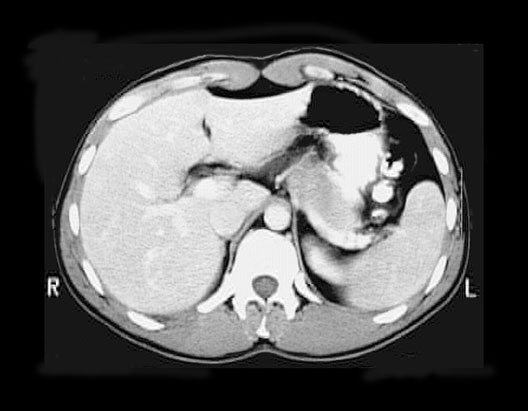

Abdominal CT

1. Liver

2. Rectus abdominis muscle

3. Linea alba

4. Stomach

5. Abdominal aorta

6. Spleen

7. Left crus of diaphragm

8. Erector spinae muscles

9. Hemiazygos vein

10. Right crus of diaphragm